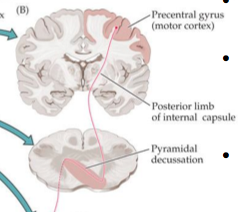

In the brainstem lateral corticospinal axons descend on the same side as their cortical origin until the

pyradmial decussation in the caudal medulla